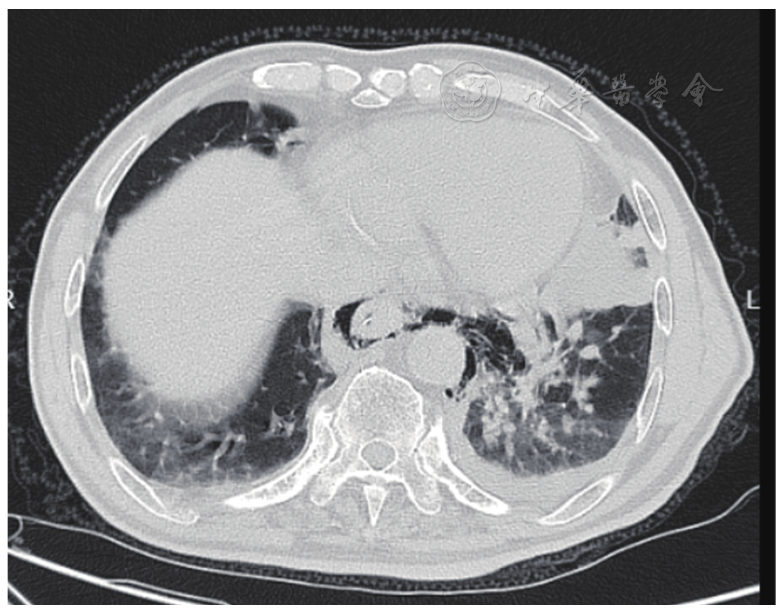

图2 入院后4天复查CT,造影剂溢出进入左侧胸腔,左侧液气胸增多。CT:计算机断层扫描